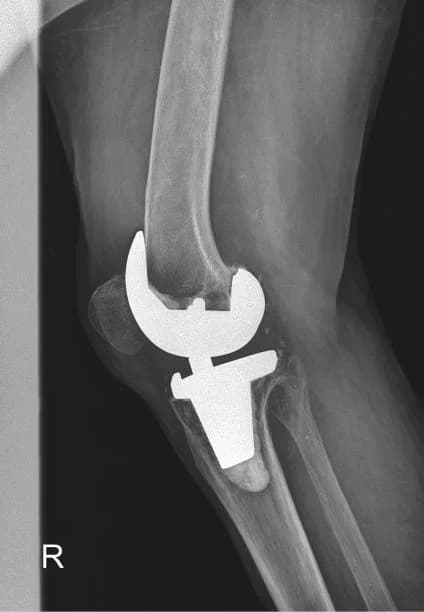

KneeKnee Replacement in South Delhi

Long-standing knee pain that limits walking or sleep can make you worry surgery is the only option. At our CR Park clinic, knee replacement is considered only when daily function is clearly limited and non-surgical care no longer helps. Most people return to walking with structured rehab. If you are looking for knee replacement in South Delhi, we explain timing and recovery in plain language. Clinic in CR Park; patients visit us from GK, Kalkaji, Nehru Place, Okhla and across South Delhi. WhatsApp us if you are unsure about timing.